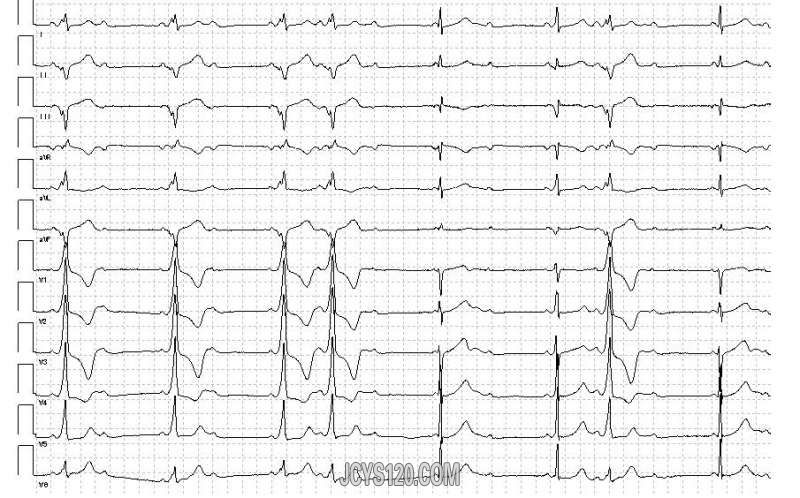

• 心电图 attach_img agree

• 斯文医生gebo 2016-1-21

• 各位老师好,帮忙分析一下这份心电图。患者女,81岁,近期感冒后出现咳喘,体温正常,双肺呼吸音粗,满布干湿罗音。心音低,律齐,各瓣膜未闻及杂音,这是今上午做的心电图,帮忙分析一下。 手机像素有点低,模糊, ...  阅读全文>